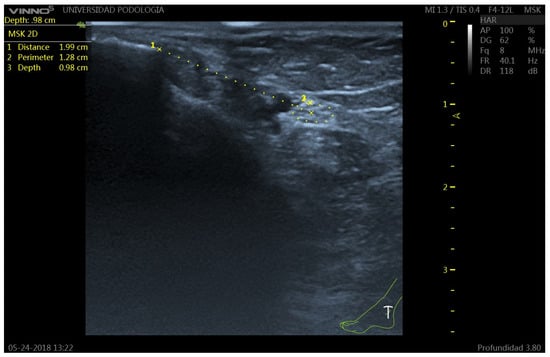

2.3. Ultrasound Protocol

- Distance (D): from the most prominent point of the medial malleolus to the center of the TN.

- Depth (d): perpendicular distance from the skin surface to the upper edge of the tibial nerve perimeter.

- Perimeter (P): measured along the outer contour of the TN.